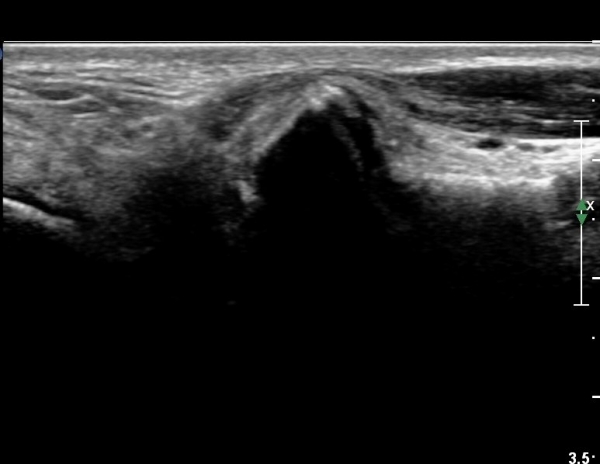

¹ß¸ñ °üÀý Á¾´Ü¸é°Ë»ç¿¡¼­ °æ¹ÌÇÑ °üÀý³» ºÎÁ¾À» º¸ÀÓ(»çÁø 1).